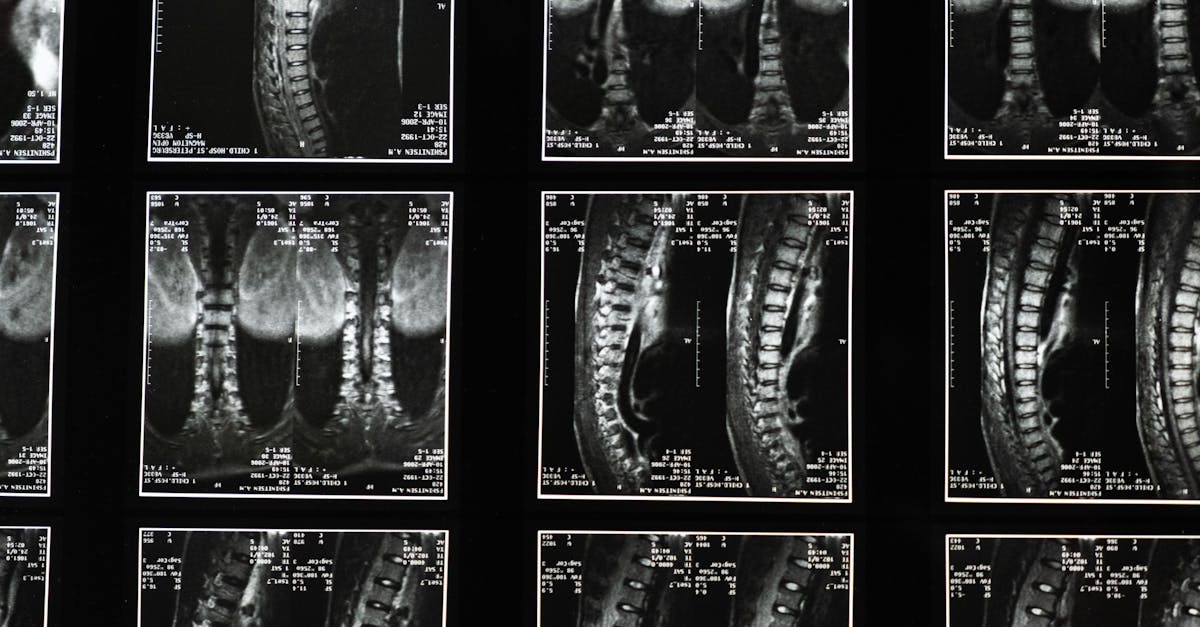

- Comprehensive initial evaluation: Patients are assessed by experts experienced in spine disorders, including an extensive review of history, imaging, and clinical findings. Utilizing evidence-based methods ensures accurate appraisal of surgical candidacy and tailored recommendations.

Around a single diagnosis of lumbar stenosis or spondylolisthesis, no two patients are alike. Careful evaluation by an experienced professional dramatically influences treatment pathways. Drawing from my 30+ years in osteopathy and spine care, I apply rigorous scientific principles, leveraging cutting-edge imaging and clinical tools to accurately assess the pathology and the patient’s overall condition.

- Identifying precise levels affected and the extent of nerve involvement

| Imaging and functional testing | Accurate diagnosis and surgical planning |